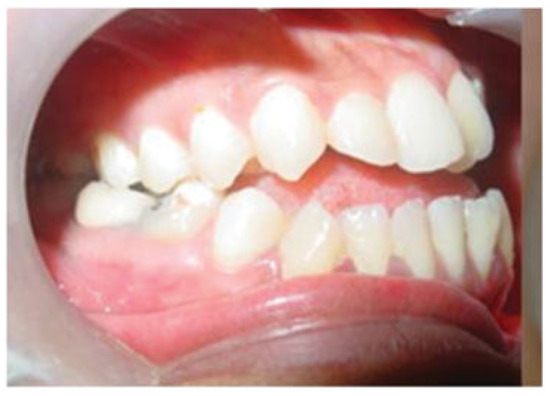

A Modified Kole's Osteotomy for Correction of Anterior Open Bite and Macrogenia in a Cleft Patient

:Surgical Method